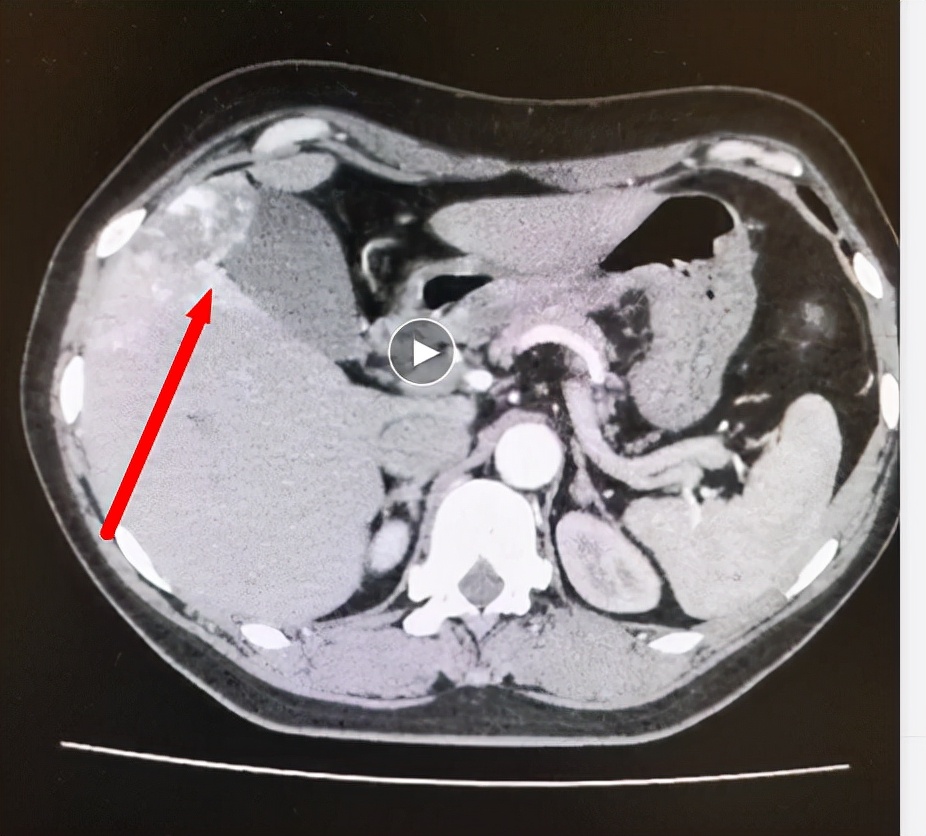

施宝民教授研究了患者的CT影像发现,非常巧合的是,血管瘤正好在胆囊床上,也就是胆囊躺在血管瘤上,而血管瘤的底部凸起正好压在胆囊上方。这种血管瘤靠近肝脏边缘、外凸非常明显,比较容易破裂,对胆囊的功能也会有影响。所以该患者既往一直患有胆囊结石、胆囊炎。

肝脏第V段血管瘤压在胆囊底部(红箭头所示)

“肝血管瘤不是真正意义上的肿瘤,而是一种团状的动静脉血管畸形,绝大多数都是良性的,恶变的几率非常低,肝脏的血管肉瘤非常少见。”施宝民教授解释,“但这位患者的肝血管瘤已经超过5cm,而且末端突出于肝外并覆盖于胆囊底部,比较容易破裂。如果破裂大出血会有生命危险,因此我们建议尽快切除。”